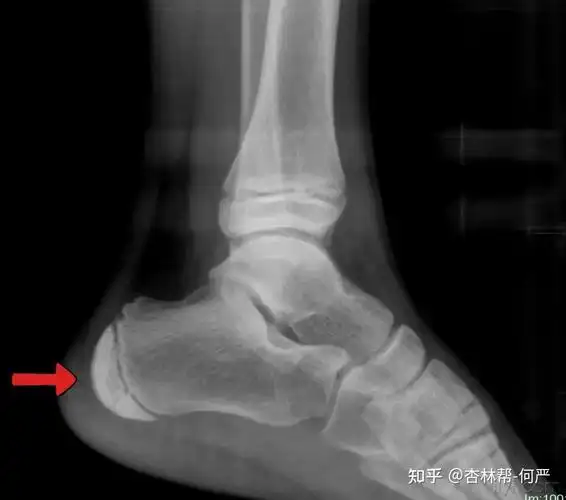

孩子脚后跟疼痛跟骨骨骺炎